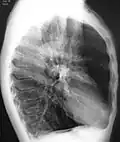

A chest X-ray is not useful to establish a diagnosis of COPD, but it is of use in either excluding other conditions or including comorbidities such as pulmonary fibrosis and bronchiectasis. Characteristic signs of COPD on X-ray include hyperinflation (shown by a flattened diaphragm and an increased retrosternal air space) and lung hyperlucency.[5] A saber-sheath trachea may also be shown that is indicative of COPD.[111]

A lateral chest X-ray of a person with emphysema, displaying barrel chest and flat diaphragm